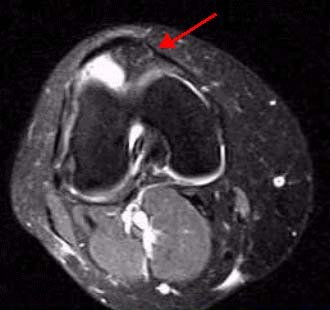

Мальчик 10 лет, не так давно перенесший незначительную травму правого коленного сустава. На рентгенограмме костные структуры целостные, лишь определяется выраженное расширение и минимальное усиление мягких тканей.  На первом представленном изображении определяется выраженное скопление жижкостного содержимого. Синовиальная оболочка утолщена с гипоинтенсивными участками.

Аксиальная томограмма Т1 после усиления Gd с жироподавлением демонстрирует диффузные и узелковые синовиальные разрастания. Очаги накопления указаны стрелками в синовиальной оболочке и в жировом тельце Гоффа.